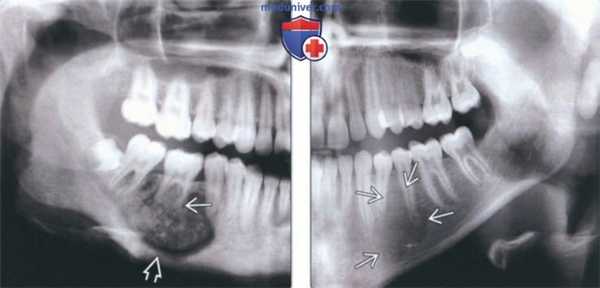

В клинику обратилась 26-летняя женщина с жалобами на медленно растущую болезненную припухлость в правой задней части нижней челюсти, которая развивается в течение последних 3 лет. Боль обладает умеренным и интермитирующим характером. При внешнем осмотре выявлена припухлость с гладкой поверхностью размерами 3 x 3 см, затрагивающая правую часть тела нижней челюсти примерно от симфиза подбородка до второго нижнего моляра с правой стороны и вызывающая выраженную асимметрию лица. Внутриротовой осмотр без особенностей, слизистая оболочка над припухлостью не изменена. Пальпаторно лимфаденопатия не обнаружена.

На ортопантомограмме определяется обширная рентгенопрозрачная зона, затрагивающая второй нижний моляр с правой стороны. Образование содержит кальцифицированные массы, приближающиеся к дистальному корню второго моляра, а так же несколько рентгеноконтрастных участков, расположенных на фоне зоны просветления. Данное образование являлось хорошо очерченным и вызывало выбухание и истончение костной ткани нижнего края нижней челюсти. (Фото 1).

Фото 1: Ортопантомограмма. Крупное однополостное рентгенопрозрачное образование, затрагивающее второй нижний моляр с правой стороны, с участками минерализации

Дифференциальный диагноз проводился с цементобластомой, остеоидной остеомой, оссифицирующей фибромой и фокальной цементно-костной дисплазией.

Впоследствии новообразование было выскоблено. Изъятая ткань, а также второй моляр были направлены на гистопатологическое исследование (Фото 2).

Гистопатологическое исследование позволило поставить диагноз агрессивной остеобластомы.

Остеобластома – это достаточно редкая опухоль кости, для которой поражение челюстных костей не является характерным. Однако описаны случаи ее возникновения в задней части нижней челюсти. Зачастую особенно сложной оказывается дифференциальная диагностика, в виду нечеткого рентгенологического и клинического облика, а так же гистологических особенностей данной опухоли, которые иногда напоминают остеосаркому.

Типичные остеобластомы являются биологически доброкачественными и ограниченно растущими, как привило не более 4 см в диаметре. Но также существует небольшая группа пограничных, более агрессивных остеобластом. Такие опухоли не могут быть классифицированы как «типичные», и поэтому они выделяются в отдельный класс поражений с наименованиями: остеобластомоподобная остеосаркома, злокачественная остеобластома или агрессивная остеобластома.

Агрессивные остеобластомы возникают в более позднем возрасте, нежели опухоли с доброкачественным течением. С клинической стороны у этих новообразований более агрессивное поведение. Они могут разрастаться в соседние ткани, а после лечение рецидивируют в 10-21% случаев, однако никогда не метастазируют. Гистологическая картина скорее напоминает остеосаркому, чем доброкачественное новообразование. Некоторые авторы заявляют, что заболевание, называемое агрессивной остеобластомой, на самом деле является высокодифференцированной остеосаркомой, напоминающей течение остеобластомы. Диагностика основывается на гистологических особенностях и клинической картине поражения.